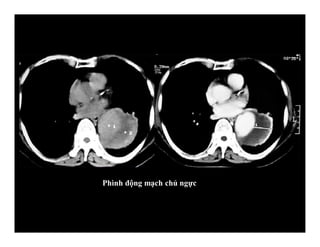

Phình động mạch chủ ngực

PreCE

Post CE 30’’

Post CE 90’’

Post CE 180’’

Khảo sát huyết động sự tăng quang